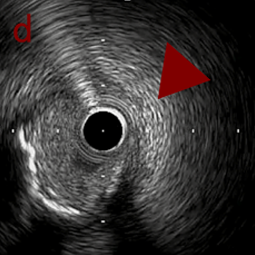

OAS low speedによる引きのsandingを3回行いIVUSを確認するとa-cでは心筋側側へのOASによる良好なbias変化と、それに伴いdの健常側への危険なbias変化を認めた。

そのためcでIVUSマーキングを行い、その点より引きで赤線のpinpoint OAS high speedを行い、dに関してはinjury回避のためにOASを当てない方針とした。

OASを行うたびに徐々に心筋側側にwire bias変化をきたし、石灰化病変部に関してはそれが良い変化となっているが、distal reference (d) に関してはinjury riskの高いbias変化となっていった。

OAS low3

OASでsandingを繰り返すことでwire biasは大きく変化することがある。

その変化は良好な変化のこともあれば危険な変化のこともある。

本症例は石灰化病変部に関してはsandingを行うことで石灰化内に食い込み、良好なbias変化をきたした。しかし、その一方でwire biasが心筋側側にかかることでdistal referenceで健常側への危険なbias変化をきたした。

OASの後、繰り返しIVUSを行うことでwire bias変化を捉えることができる。またIVUSマーキングすることで、ピンポイントに削りたいところだけを安全に削ることができる。